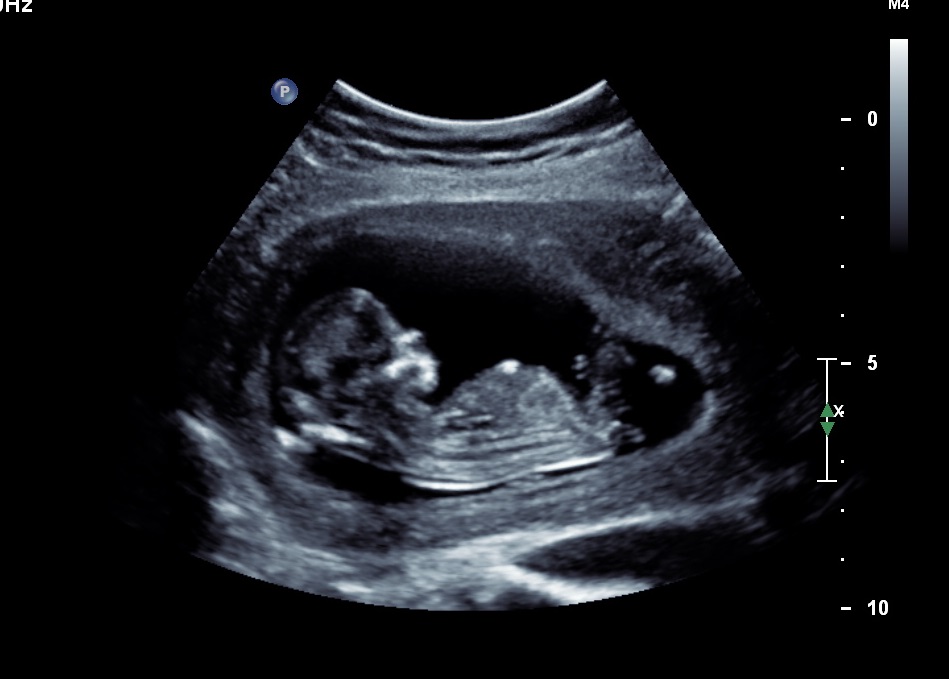

Please help! I am rubbish at reading ultrasounds! Can anyone see the nub and read it for me please? My friend thought she saw it and thought it was a boy angle....but my gut says girl. Hubby isn't letting me find out at the 20w scan so this is the only clue I get!! Thanks so so much.

I'm 12w3d by dates, 13w3d by scan.